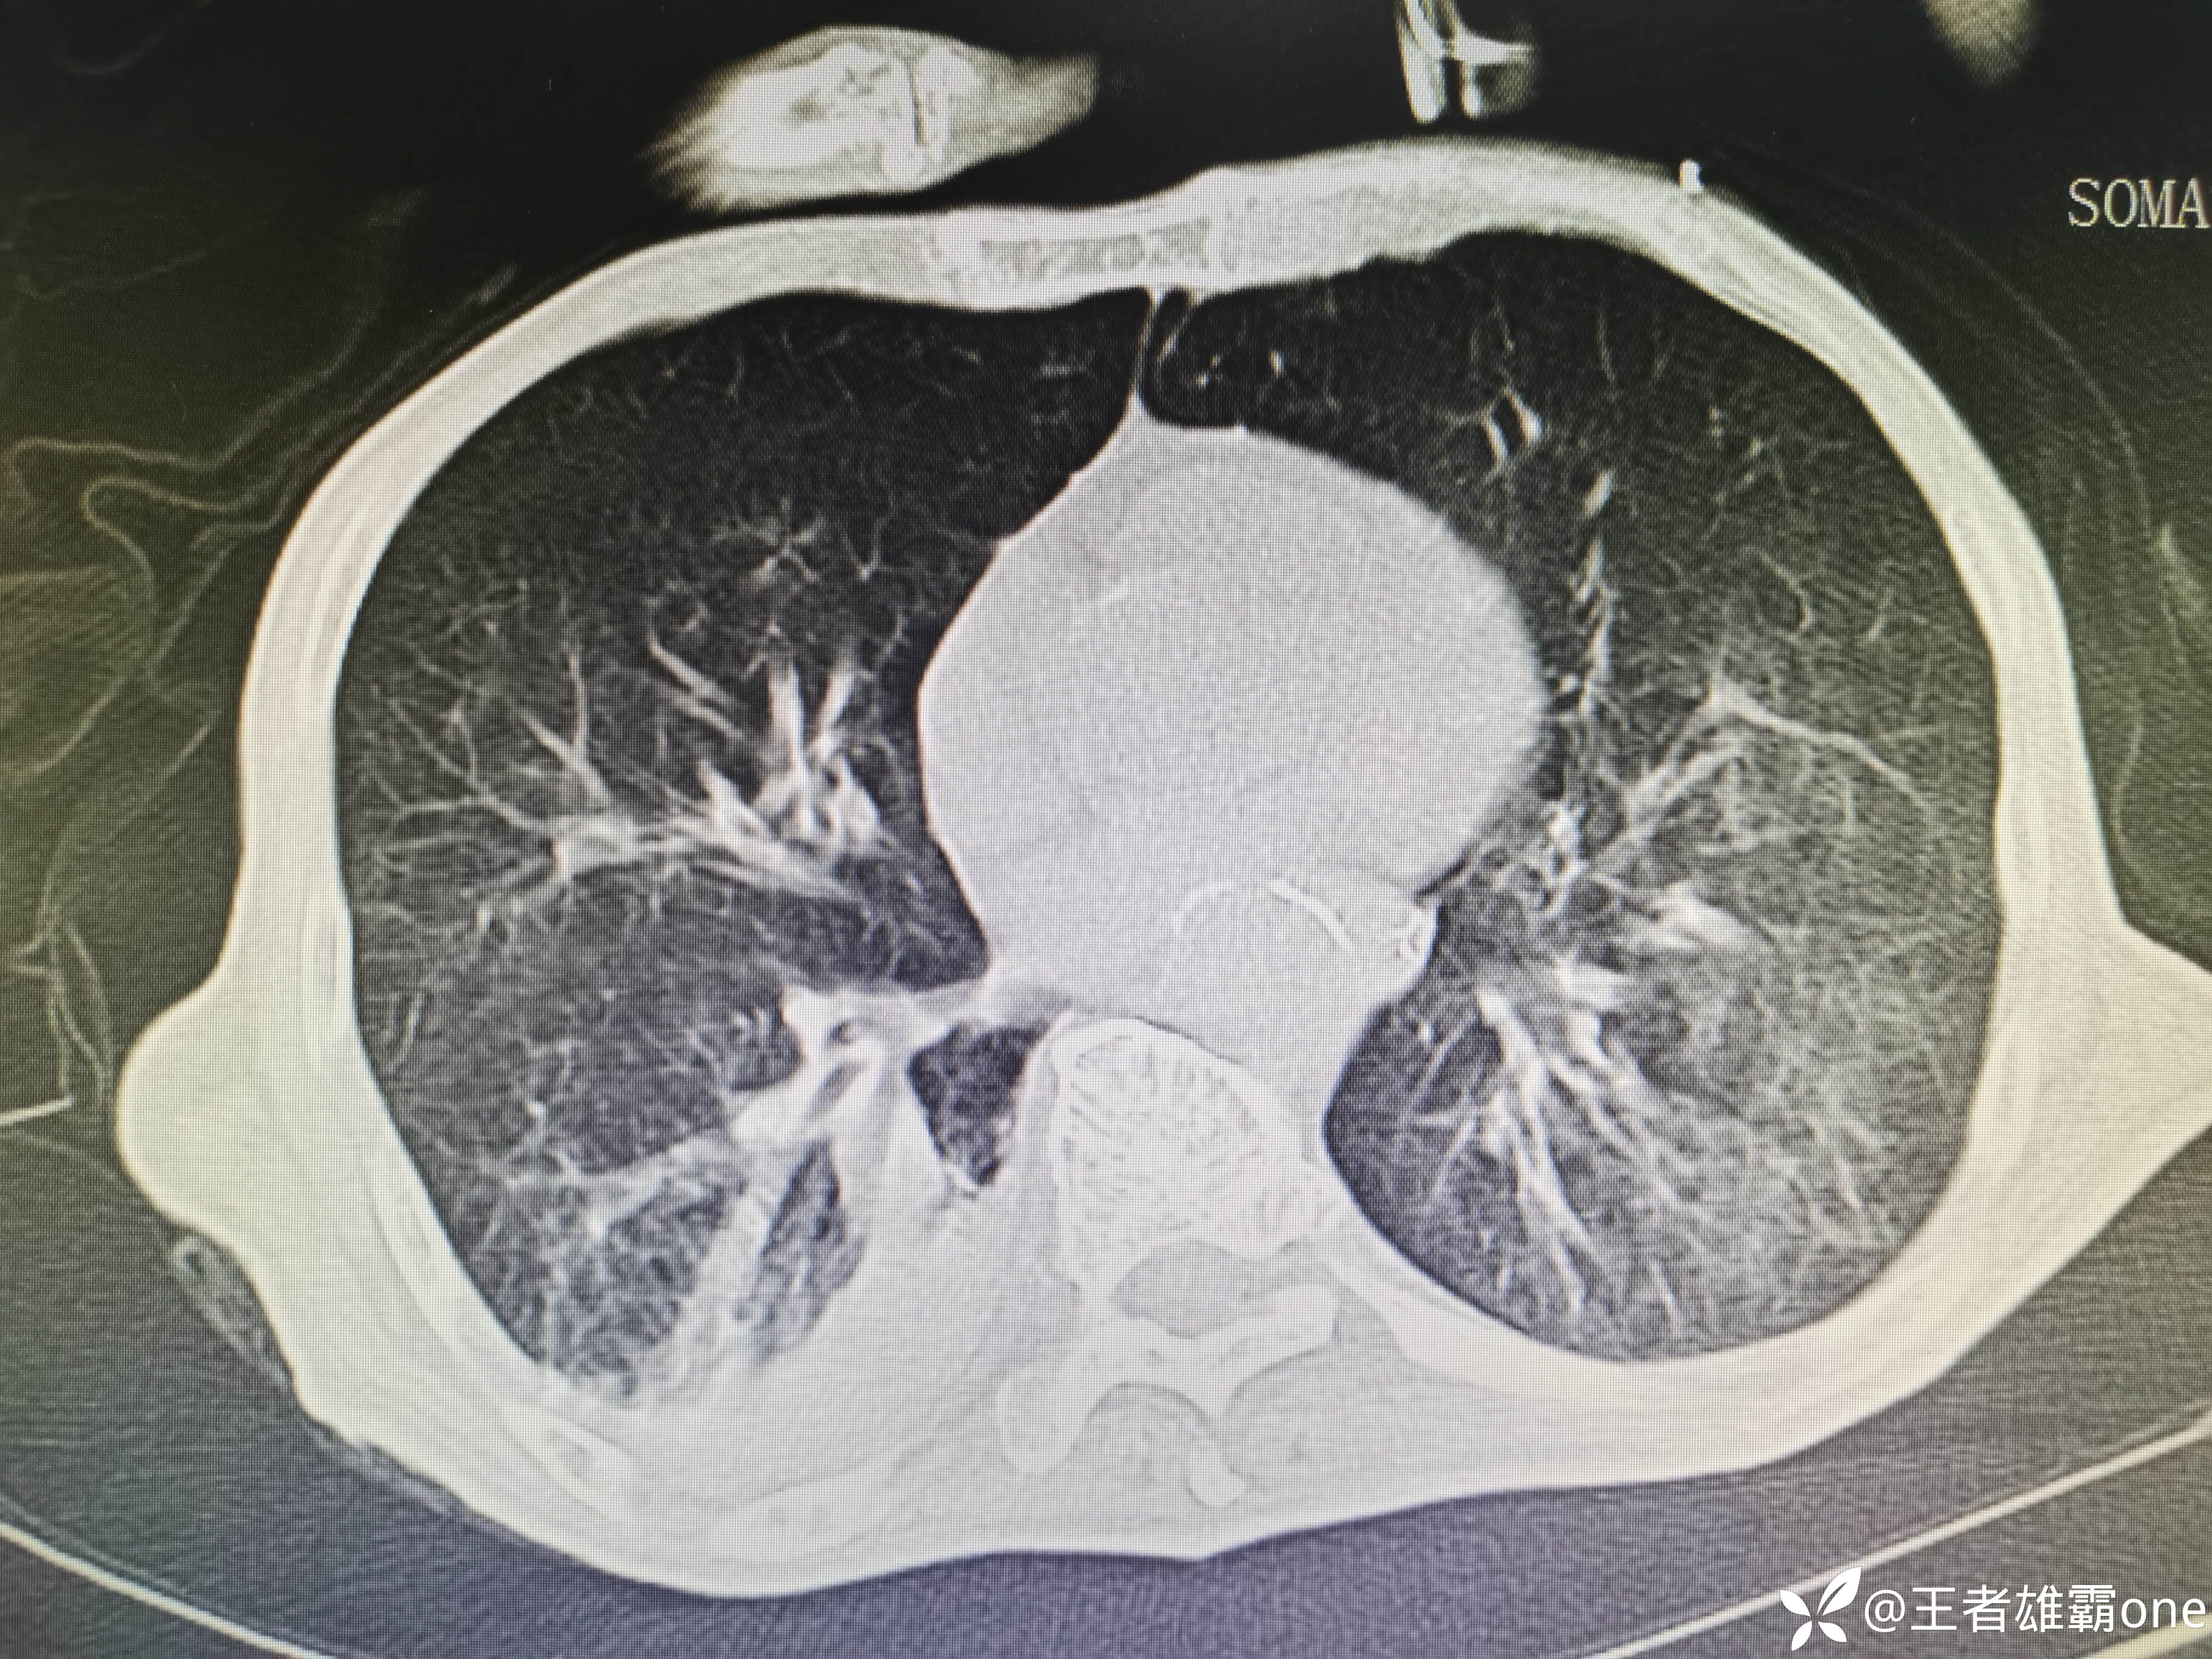

入院时胸部CT:

具体图片: